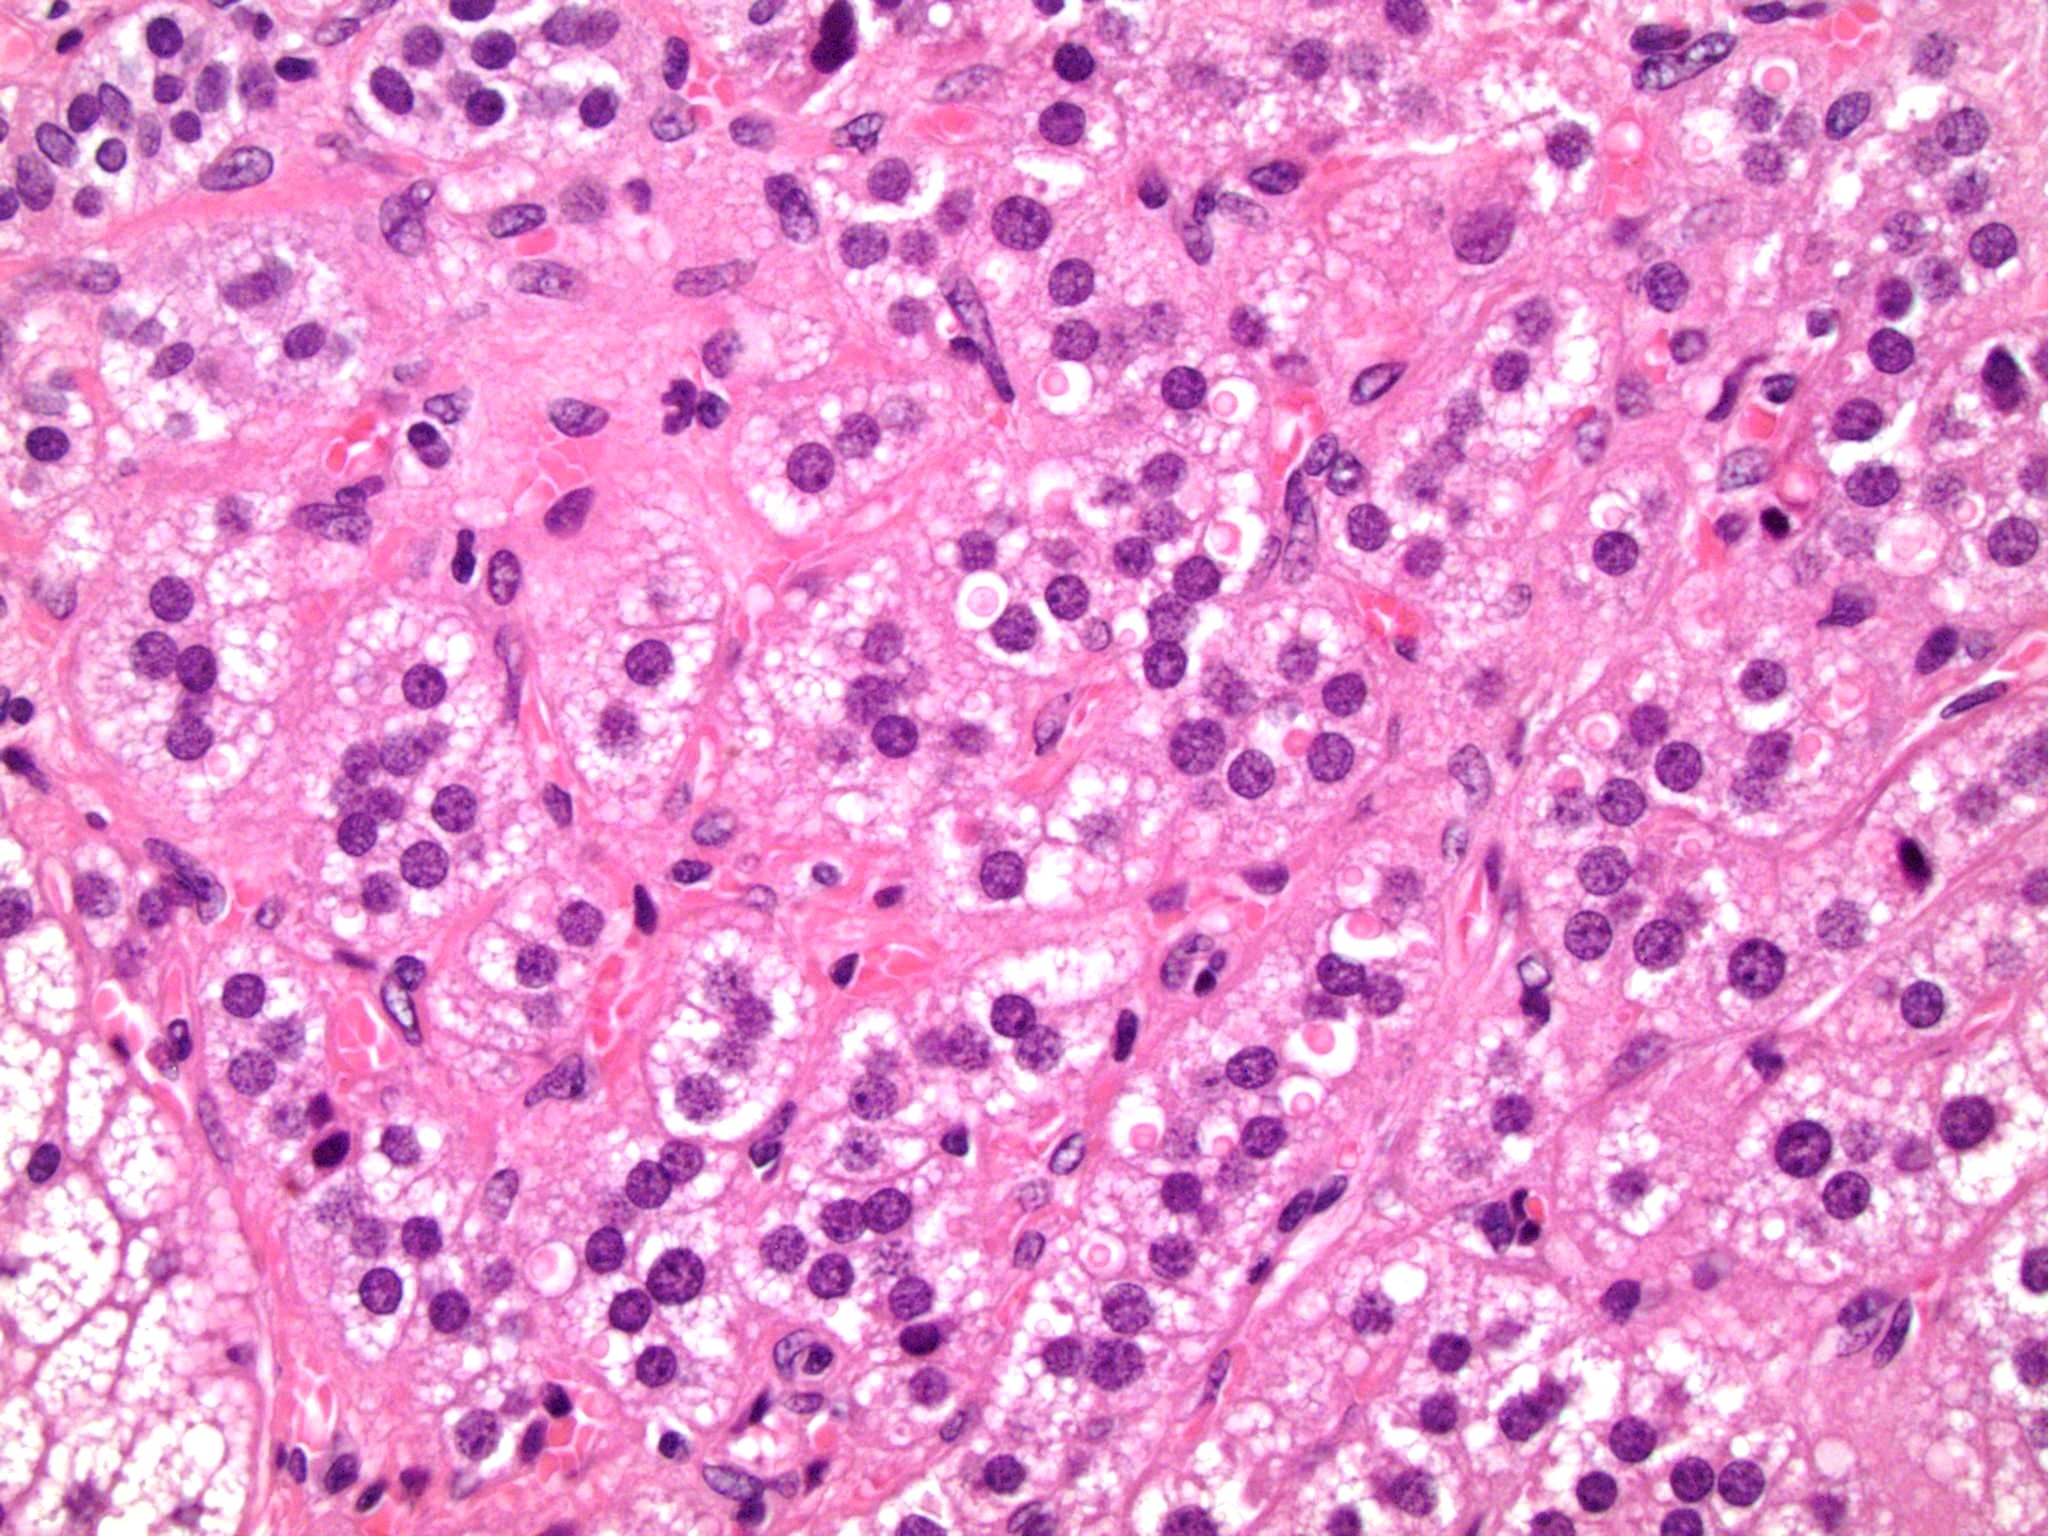

Microscopic (histologic) description

- In comparison to surrounding adrenal gland, adenoma cells are larger with different cytoplasm, increased variation in nuclear size

- Distinct cell borders, cells have abundant foamy cytoplasm reminiscent of zona fasciculata

- Balloon cells: clusters of cells with enlarged lipid-rich cytoplasm (seen in Cushing syndrome)

- Histologic variants: oncocytic, myxoid

Microscopic (histologic) images

Contributed by Xiaoyin "Sara" Jiang, M.D., Debra Zynger, M.D., @Andrew_Fltv on Twitter and @SueEPig on Twitter